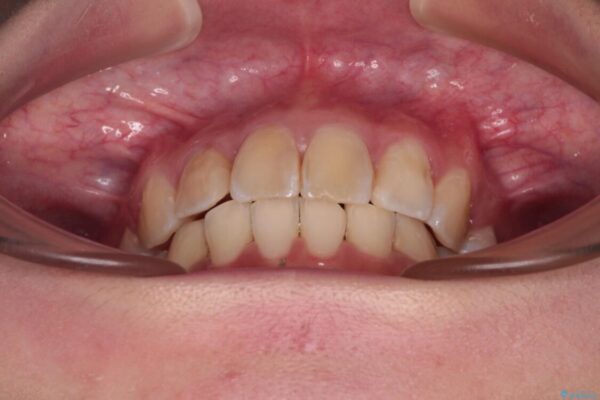

内側に倒れ込んだ歯や下の前歯が隠れてしまうほどの咬み合わせを改善したいとのことで来院された患者様です。

治療前

• デコボコと深い咬み合わせ ワイヤー装置での抜歯矯正 治療前画像